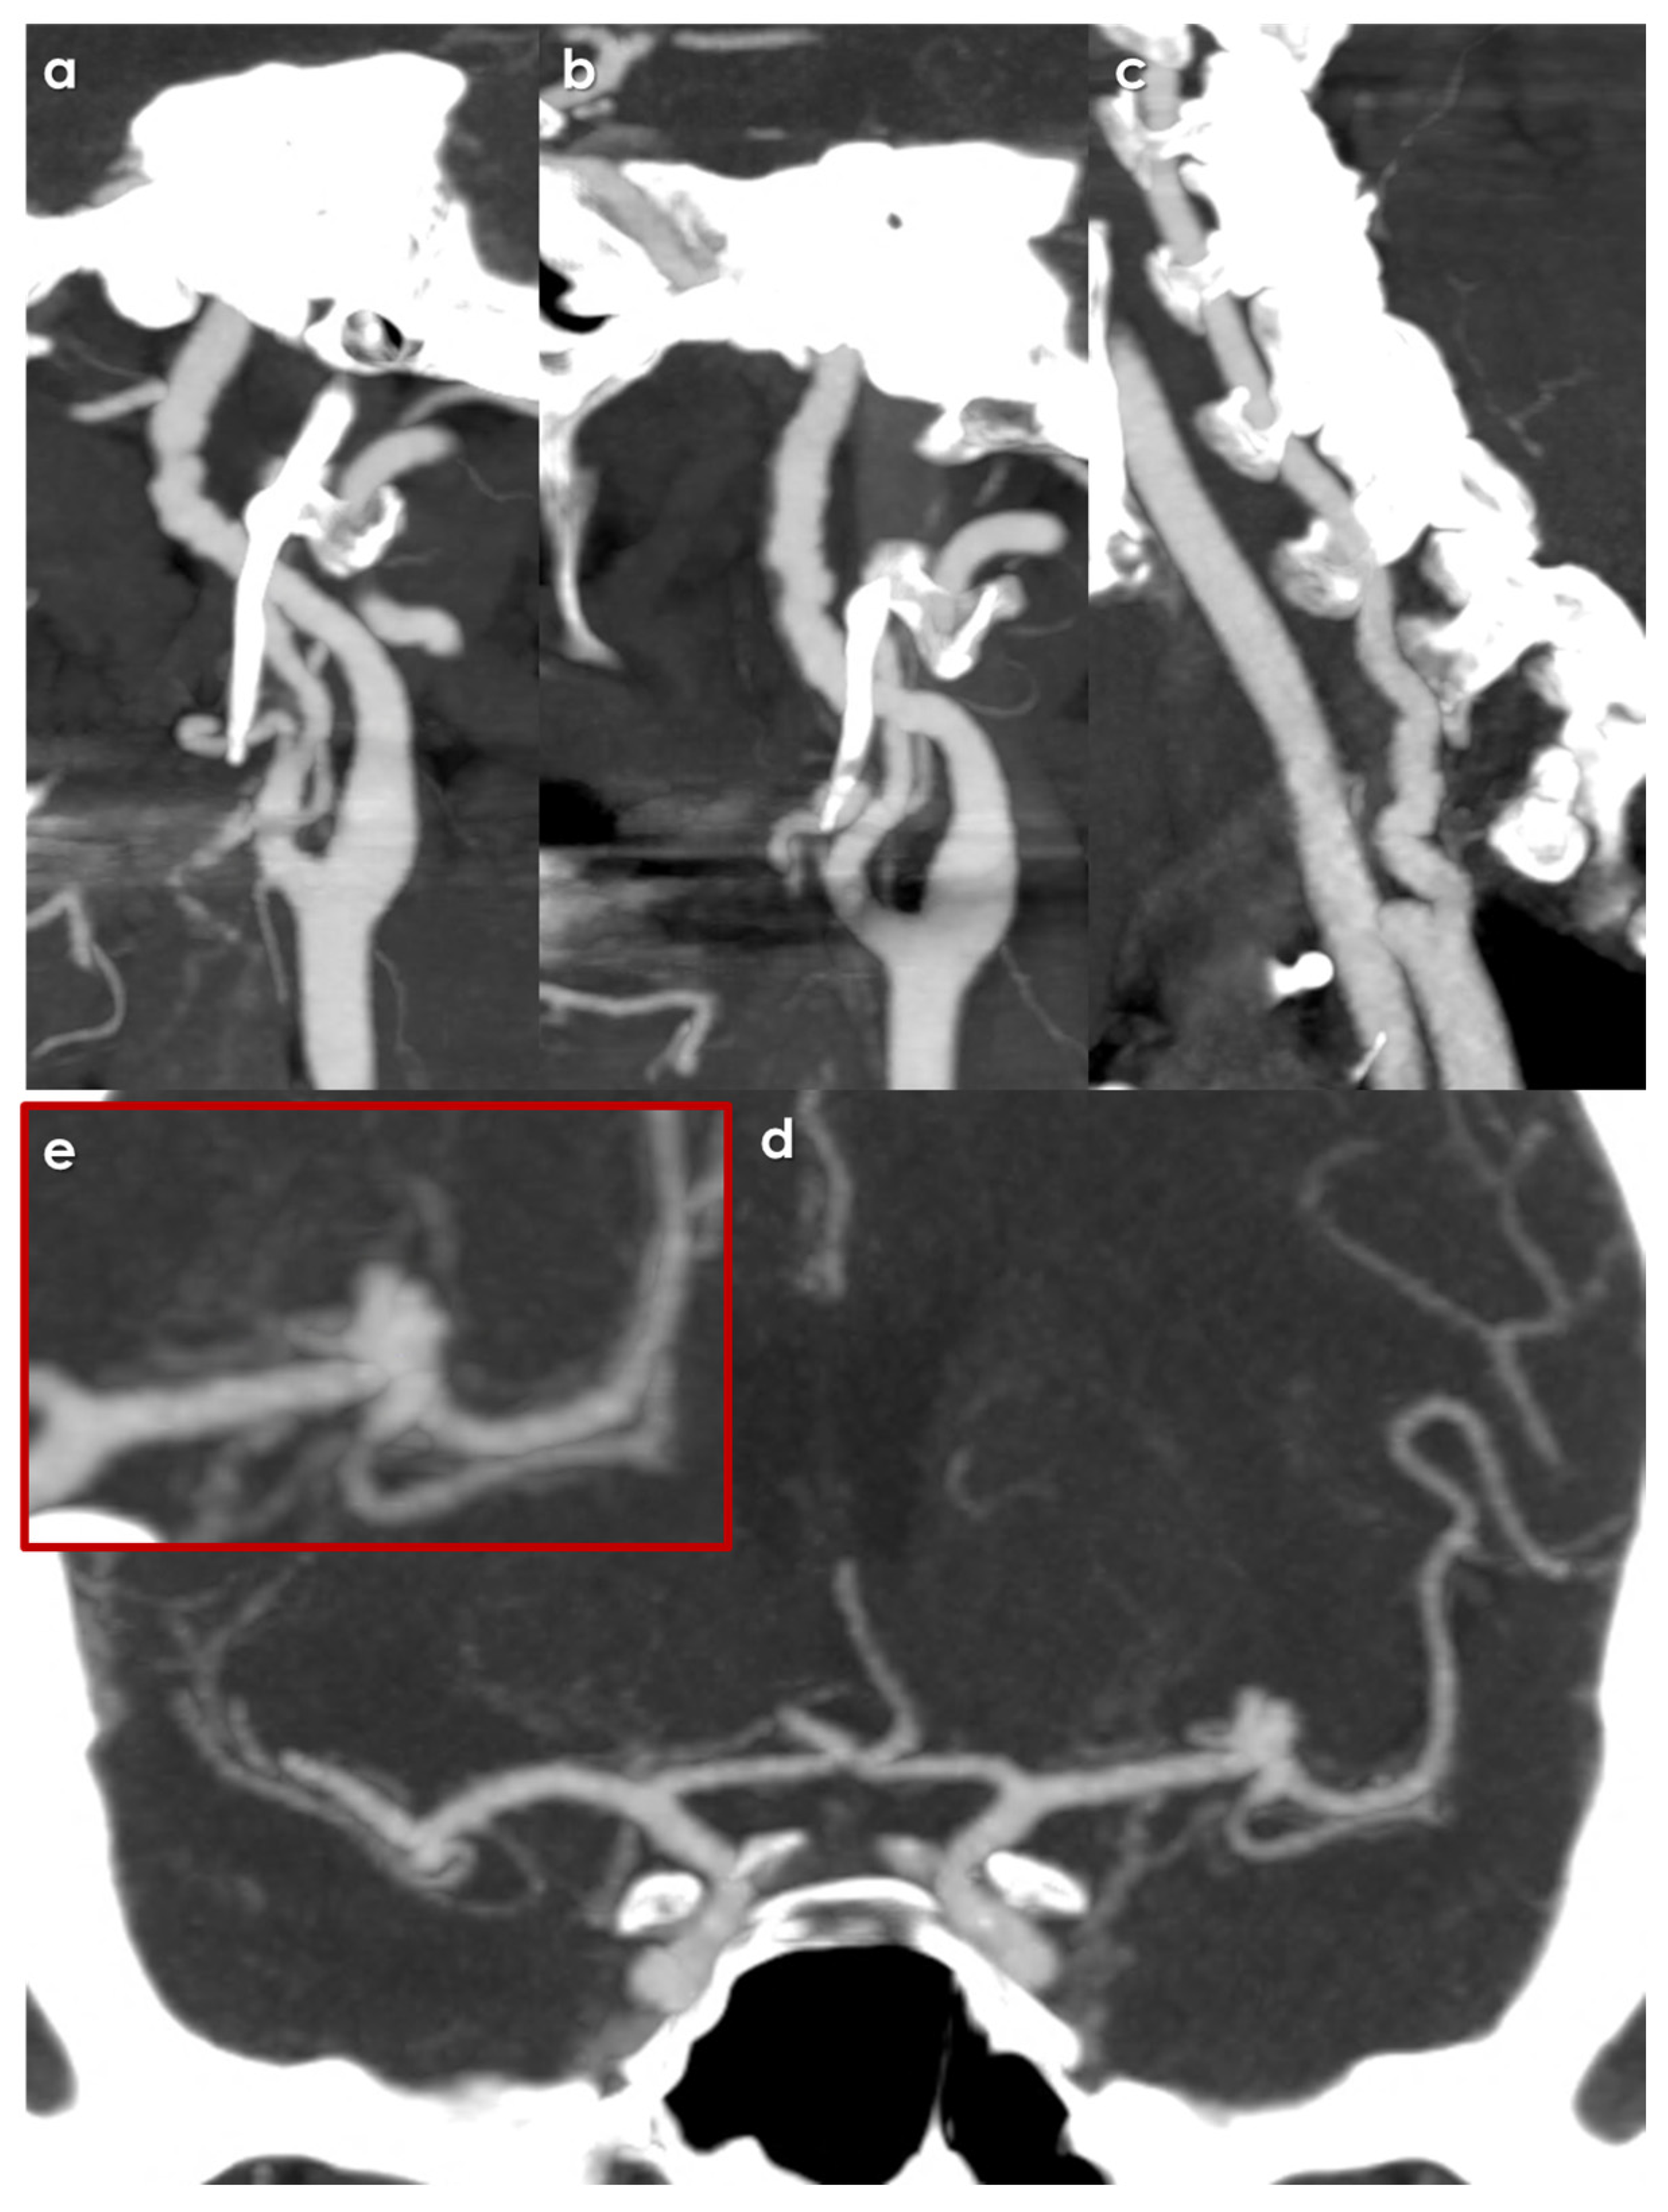

2. Materials and Methods

3. Results

3.3. Features of Intracranial Aneurysms

- Location of Aneurysms: The distribution of IAs was notable, with a significant number located in areas typically associated with higher risks of rupture. A substantial 41% of the identified intracranial aneurysms were located in the intradural segments of the ICA, which is considered a high-risk area, along with 12% in the posterior communicating artery and 9% in posterior circulation arteries.

3.4. Treatment Issues